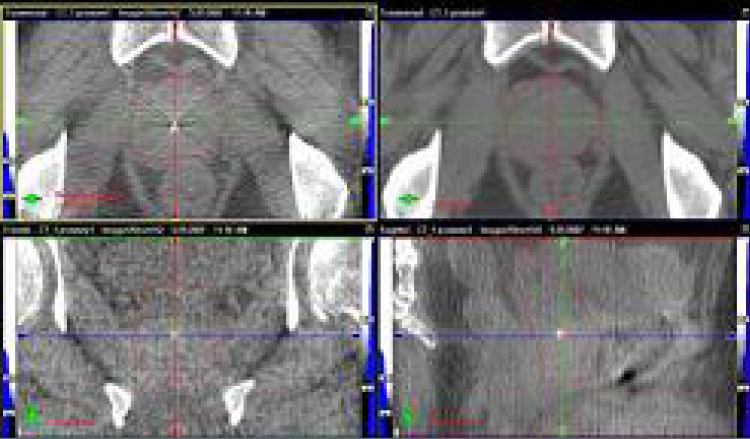

OBIは治療機側⾯に連結したX線透視装置で、治療寝台上で放射線照射を受ける状態での治療位置照合を可能とします。また、回転撮影することにより寝台上で治療直前のCT画像(CBCT︓cone-beam CT)も取得できます。これによりX線透視では⾒えない軟部臓器や腫瘍病巣の動きを詳細に観察することが可能になり、治療の精度をさらに⾼めることができます。

CBCT画像の例(前⽴腺)

治療計画時との画像と治療寝台上でのずれをCT画像で確認内部臓器や腫瘍の動き調節することが可能 精度1mm